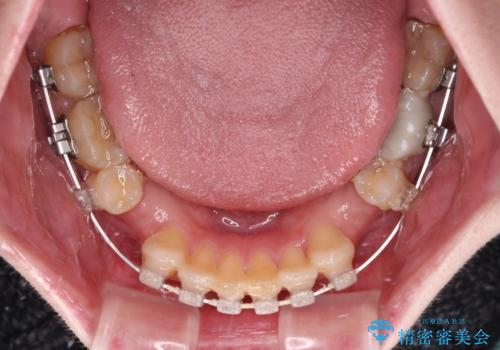

- 前歯のデコボコと、その結果むし歯が進行していることを気にして来院された患者様です。

前歯や奥歯の根管治療を行い、その後上下左右の第一小臼歯4本を抜歯してワイヤー装置にて矯正治療を行うこととしました。

矯正治療後には、根管治療を行った歯をオールセラミッククラウンにて補綴治療を行うこととしました。